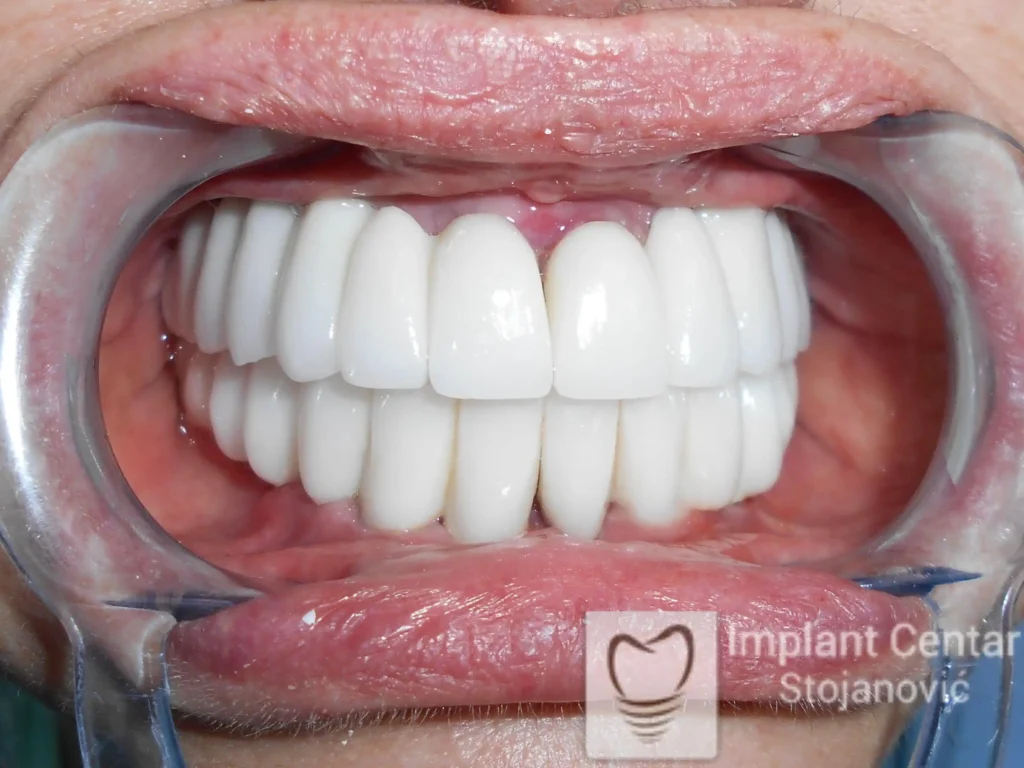

Tokom perioda oseointegracije, pacijent je bio zbrinut fiksnim privremenim krunicama, čime je već pet dana nakon intervencije obezbeđena potpuna funkcionalna i estetska rehabilitacija. Nakon završetka perioda integracije implantata, izrađeni su definitivni cirkonijum-keramički mostovi na implantatima.

Pacijent je izuzetno zadovoljan postignutim rezultatom, navodeći da po prvi put jasno oseća svoje nepce tokom žvakanja, kao i da se smeje sa punim samopouzdanjem.